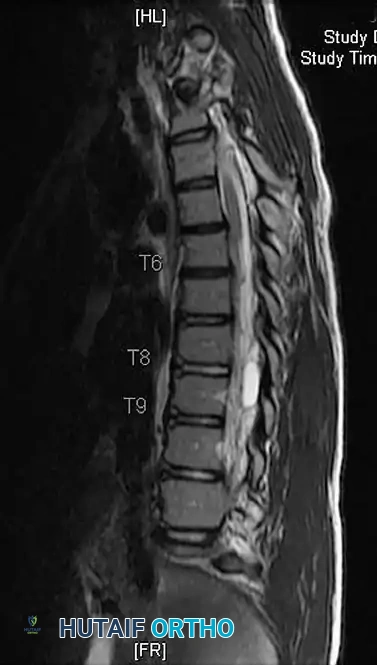

Surgical Warning: A meticulous neurological examination is mandatory. Asymmetric abdominal reflexes, hyperreflexia, or cavus foot deformities are red flags for intraspinal anomalies (e.g., syringomyelia, tethered cord, Chiari malformation) and necessitate a total spine MRI prior to any surgical intervention.

Sagittal Plane Assessment

Sagittal balance is equally critical. Thoracic hypokyphosis is a hallmark of AIS. Normal thoracic kyphosis ranges from 20 to 40 degrees, and lumbar lordosis ranges from 40 to 60 degrees.

Fig. 15: Evaluation of sagittal alignment, including thoracic kyphosis and lumbar lordosis.